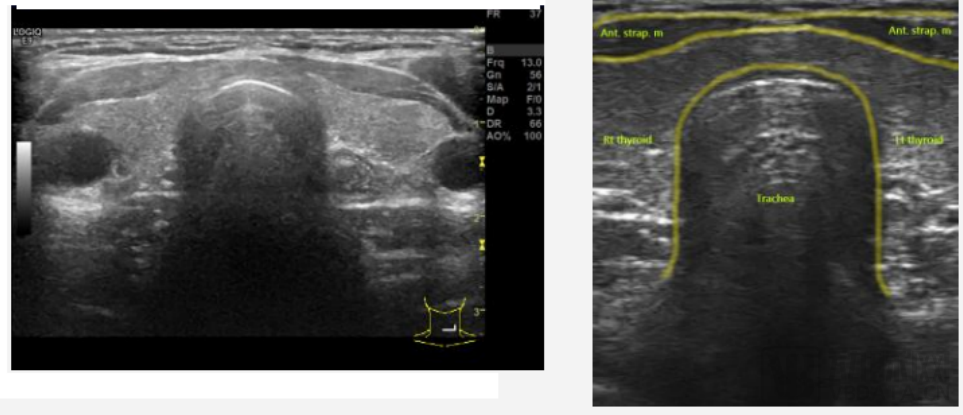

医银甲状腺人工智能辅助诊断系统可提供智能、快速、精准地位置坐标

其不仅可以精准、快速标定结节的方框位置坐标、结节的轮廓位置坐标,还能诊断结节属性包括成分、回声、边缘、强回声和纵横比,根据结节属性打分参照 TI-RADS 分类系统进行打分和评级,智能判断结节的良恶性。

当系统预测结果为结节时还能预测是否推荐消融诊疗。此外,该系统还可进行甲状腺有无弥漫性病变诊断。